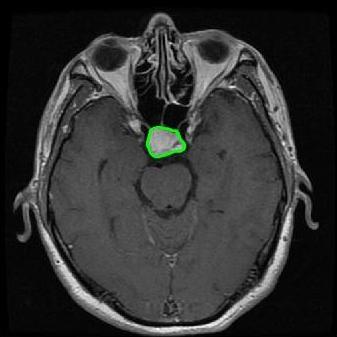

From the above discussions, we have discovered the significant potential of applying Retinex theory to image segmentation and explored its fundamental differences from traditional models. Traditional image segmentation models typically focus on the impact of intensity information on the segmentation results. Therefore, when faced with complex segmentation scenarios, the segmentation results are often affected by lighting, artifacts, and unclear boundaries in the image. As shown in Fig. 1, we present the results of the classical local model LIF [ZHANG20101199] for segmenting brain tumor images along with surrounding tissue edema. The irregular ring-like enhancement caused by the edematous tissue leads to irregular boundaries and low contrast in the images. Consequently, the LIF model can only identify the central necrotic and liquefied regions of the tumor, failing to detect the boundaries and becoming trapped in local minima. In this paper, we draw inspiration from the Retinex theory, which is widely applied in the field of image enhancement. According to Retinex theory, the reflectance component characterizes the intrinsic structural properties of the observed image and preserves texture information independent of illumination variations. By integrating this reflectance component into the level set framework, our model achieves robust segmentation of medical images even under severe intensity inhomogeneity. In addition, a linearized Structural-Prior is proposed to restore intensity consistency and capture local geometric features, thereby improving boundary localization in complex or blurred regions. Furthermore, a relaxed binary level set representation is employed to enhance robustness against noise and to enable accurate tracking of complex contours. Based on these innovations, we propose a novel variational reflectance-based level set model (RefLSM) that simultaneously corrects bias fields and performs segmentation. Experimental results demonstrate that RefLSM significantly outperforms conventional level set methods in both segmentation accuracy and robustness. We present the results of our model segmenting the two brain tumor images mentioned above in Fig. 2.

To address the challenge of segmenting images with severe intensity inhomogeneity, we propose a linearized structural prior that directly operates on the reflectance component . Reflectance-based structural information is more robust to illumination variations and bias field distortions, helping preserve weak edges and subtle anatomical boundaries. As shown in Fig. 2, our method can accurately delineate tumor boundaries and surrounding edema even under severe inhomogeneity, where traditional intensity-based models often fail. The proposed prior aligns smoothed reflectance gradients with data-driven directions, enhancing inter-region contrast, preserving weak edges, and stabilizing the evolution of . Formally, we define the linear structure operator as the gradient field of the smoothed reflectance:

Fig. 4 displays the visual comparison results for segmenting eight brain tumor MR images between the RefLSM and three representative models: the RESLS [8765635], ALF[MA2019201], and L1 model[LIU2019193]. These images exhibit severe intensity inhomogeneity and noise attributable to inconsistent bias field and imaging equipment. The initial level set function (LSF) initialization was consistent across all models, as shown in Fig. 4 (a), which illustrates the initial placement of the zero level contour. For visual clarity, we included the ground truth in Fig. 4 (f). The segmentation outcomes from the RESLS, ALF, and L1 methods are presented in Fig. 4 (b), (c), and (d), respectively.

It is evident from the first and last columns of Fig. 4 (b) that the ALF model tends to become trapped in local minima under severe intensity inhomogeneity. Furthermore, segmentation results presented in the columns 1-4 of Fig. 4 (b) and (c) reveal that both the ALF and L1 models mistakenly segment small isolated or irrelevant regions due to the effects of irregular intensity patterns. Additionally, when weak boundaries are present, as seen in the 1st and 3rd columns of Fig. 4, the RESLS, ALF, and L1 methods fail to accurately identify object boundaries. Consequently, the zero level contours of these models deviate significantly from the objects throughout the level set evolution, causing drastic misalignment after further iterations.

In stark contrast, our proposed method exhibits greater robustness against images exhibiting severe intensity inhomogeneity and weak boundaries. The proposed prior constraint term effectively corrects for intensity inhomogeneity, while the proposed binary level set adeptly reduces noise during the segmentation process.